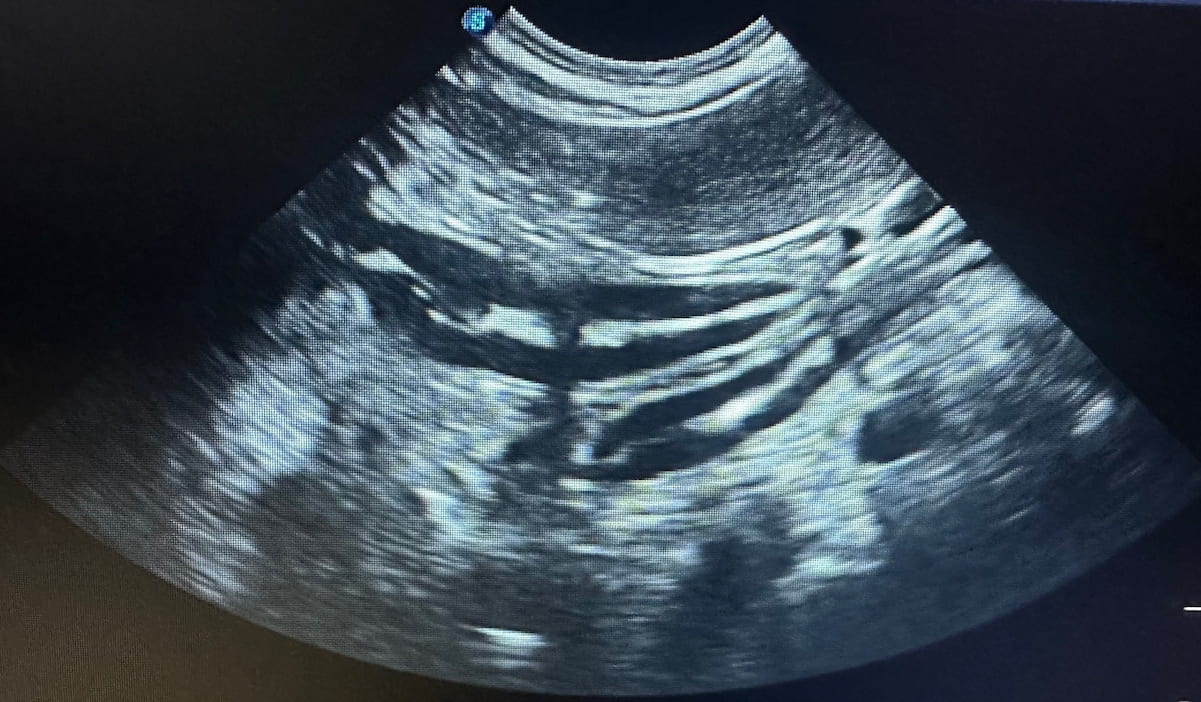

Ultraschalluntersuchung eines Hundes in der Tierarztpraxis vet4balance in Arnsberg

Unsere Ultraschalluntersuchung liefert in Arnsberg umfassende Informationen über das Körperinnere bei Hunden. Wir untersuchen die Organe, erfassen die umliegenden Gewebestrukturen und erkennen Flüssigkeitsansammlungen und andere Auffälligkeiten frühzeitig. Unsere Ultraschalldiagnostik ist für Ihren Hund völlig schmerz- und strahlenfrei.